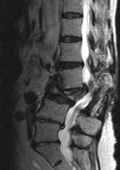

Die Therapie von Verletzungen der Hals-, Brust- und Lendenwirbelsäule sowie der angrenzenden Strukturen erfordert häufig besondere Kenntnisse in der Akutbehandlung und Rehabilitation. Gerade bei Mehrfachverletzten kann auch ein interdisziplinäre Vorgehen notwendig werden. Ziel ist die Wiederherstellung der Anatomie und Funktion und damit Erreichen einer größtmöglichen Lebensqualität. Dennoch ist eine vollständige Restaurierung verletzter Strukturen nicht immer möglich, insbesondere wenn Schädigungen des Nervensystems vorliegen. Ein besonderes Augenmerk ist im Rahmen der demographischen Entwicklung auf die Alterstraumatologie zu richten.

Therapeutisch muss dass Behandlungsspektrum neben konservativen Maßnahmen und Rehabilitation alle operativen Techniken beinhalten. Dies bedeutet neben den operativen Zugängen von hinten auch die Beherrschung sämtlicher Verfahren von vorne oder der Seite durch Bauch, Brustraum und Hals sowie an den angrenzenden Strukturen wie z. B. Becken, Schädel oder Rippen. Implantate können zunehmend auch minimalinvasiver oder endoskopisch eingebracht werden. Für besondere Formen von Wirbelkörperbrüchen, insbesondere bei Osteoporose, stehen Stabilisierungstechniken mit sogenanntem Knochenzement zur Verfügung.